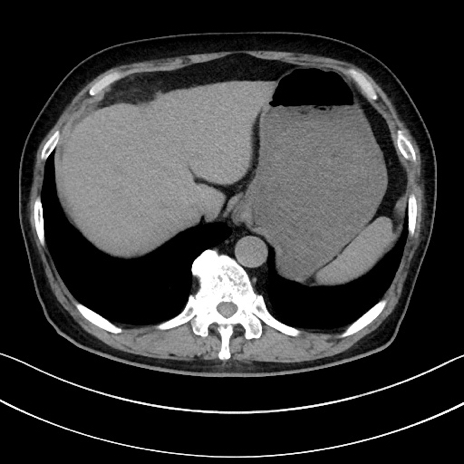

症例15(横断像)

【症例】70歳代男性

【主訴】腹痛

【現病歴】今朝から腹痛あり。全体的に痛い。特に左上の方。排ガスが今日はない。冷や汗が出る。

【既往歴】直腸癌術後

【身体所見】左側腹部〜上腹部に圧痛あり。腹膜刺激症状明らかなではない。軽度反跳痛。左下腹部に術後瘢痕あり。

【データ】WBC 7700、CRP 0.02